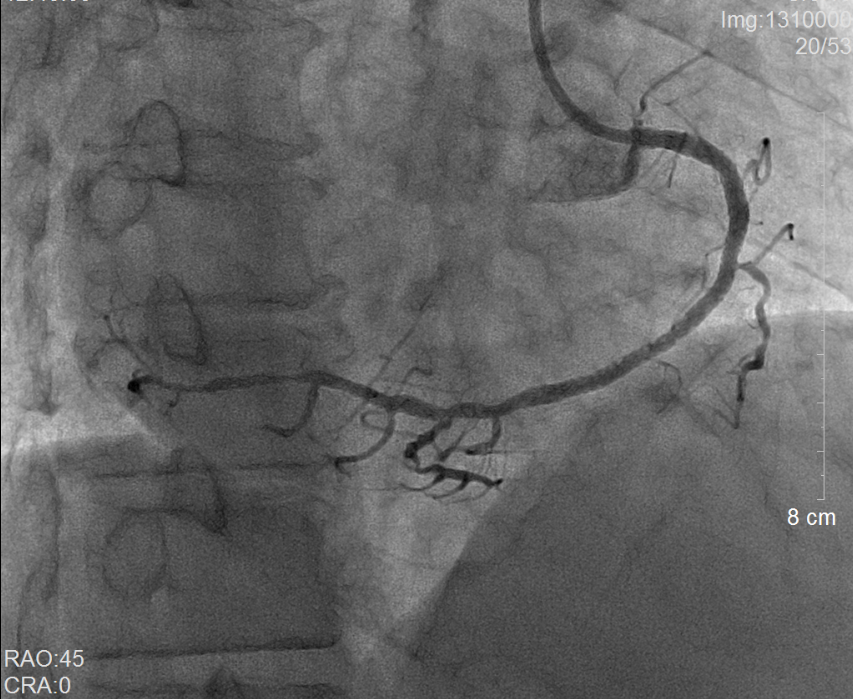

术前冠脉造影提示右冠状动脉弥漫性病变                 术后冠脉造影提示右冠状动脉血流通畅